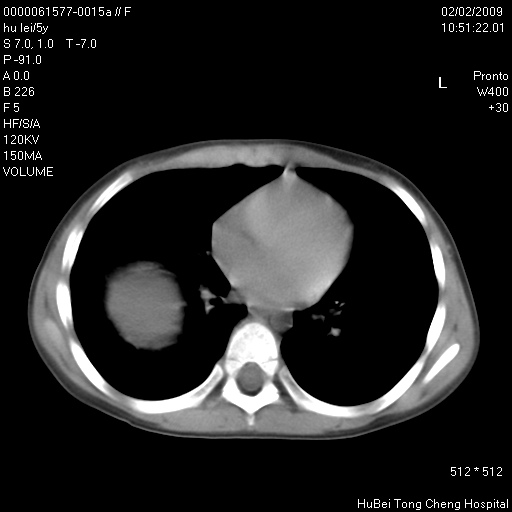

标题: PED1732:M5Y,右肺囊性占位!

患者:男,5。无明显不适,拍胸片考虑右肺囊肿。

行ct扫描,图象如下:

病灶与前胸壁和右上纵隔、叶间裂界限不清,病灶前缘及内侧缘看不到正常的肺组织,不能排除包裹性积液。